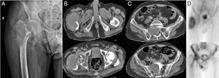

Figura 1: Cazul unei femei de 66 de ani, cu probleme de sănătate complexe, care a suferit o fractură patologică la nivelul humerusului din cauza unei metastaze. (A) Evidențiază metastaza osteolitică din humerus. (B) Imagine scintigrafică ce arată răspândirea sistemică. (C) Imagine postoperatorie care prezintă o tijă centromedulară utilizată pentru osteosinteză, permițând mișcarea imediată a brațului.

Figura 3: Bărbat de 69 de ani cu metastaze avansate la nivelul femurului proximal și sacrumului. Imaginea arată osteoliză semnificativă, indicând riscul iminent de fractură patologică. (A) Prezintă o tu-

moră osteolitică în femur, iar B și C arată scanări CT care evidențiază extinderea metastazelor în femur și sacrum. Scintigrafia osoasă (D) oferă dovezi suplimentare ale răspândirii extinse a bolii. Din cauza prezenței unei tumori inoperabile, pacientul a urmat un plan de tratament pentru ameliorarea simptomelor și îmbunătățirea calității vieții, care a inclus radioterapie și ablație cu radiofrecvență pentru reducerea durerii și stabilizarea osului.